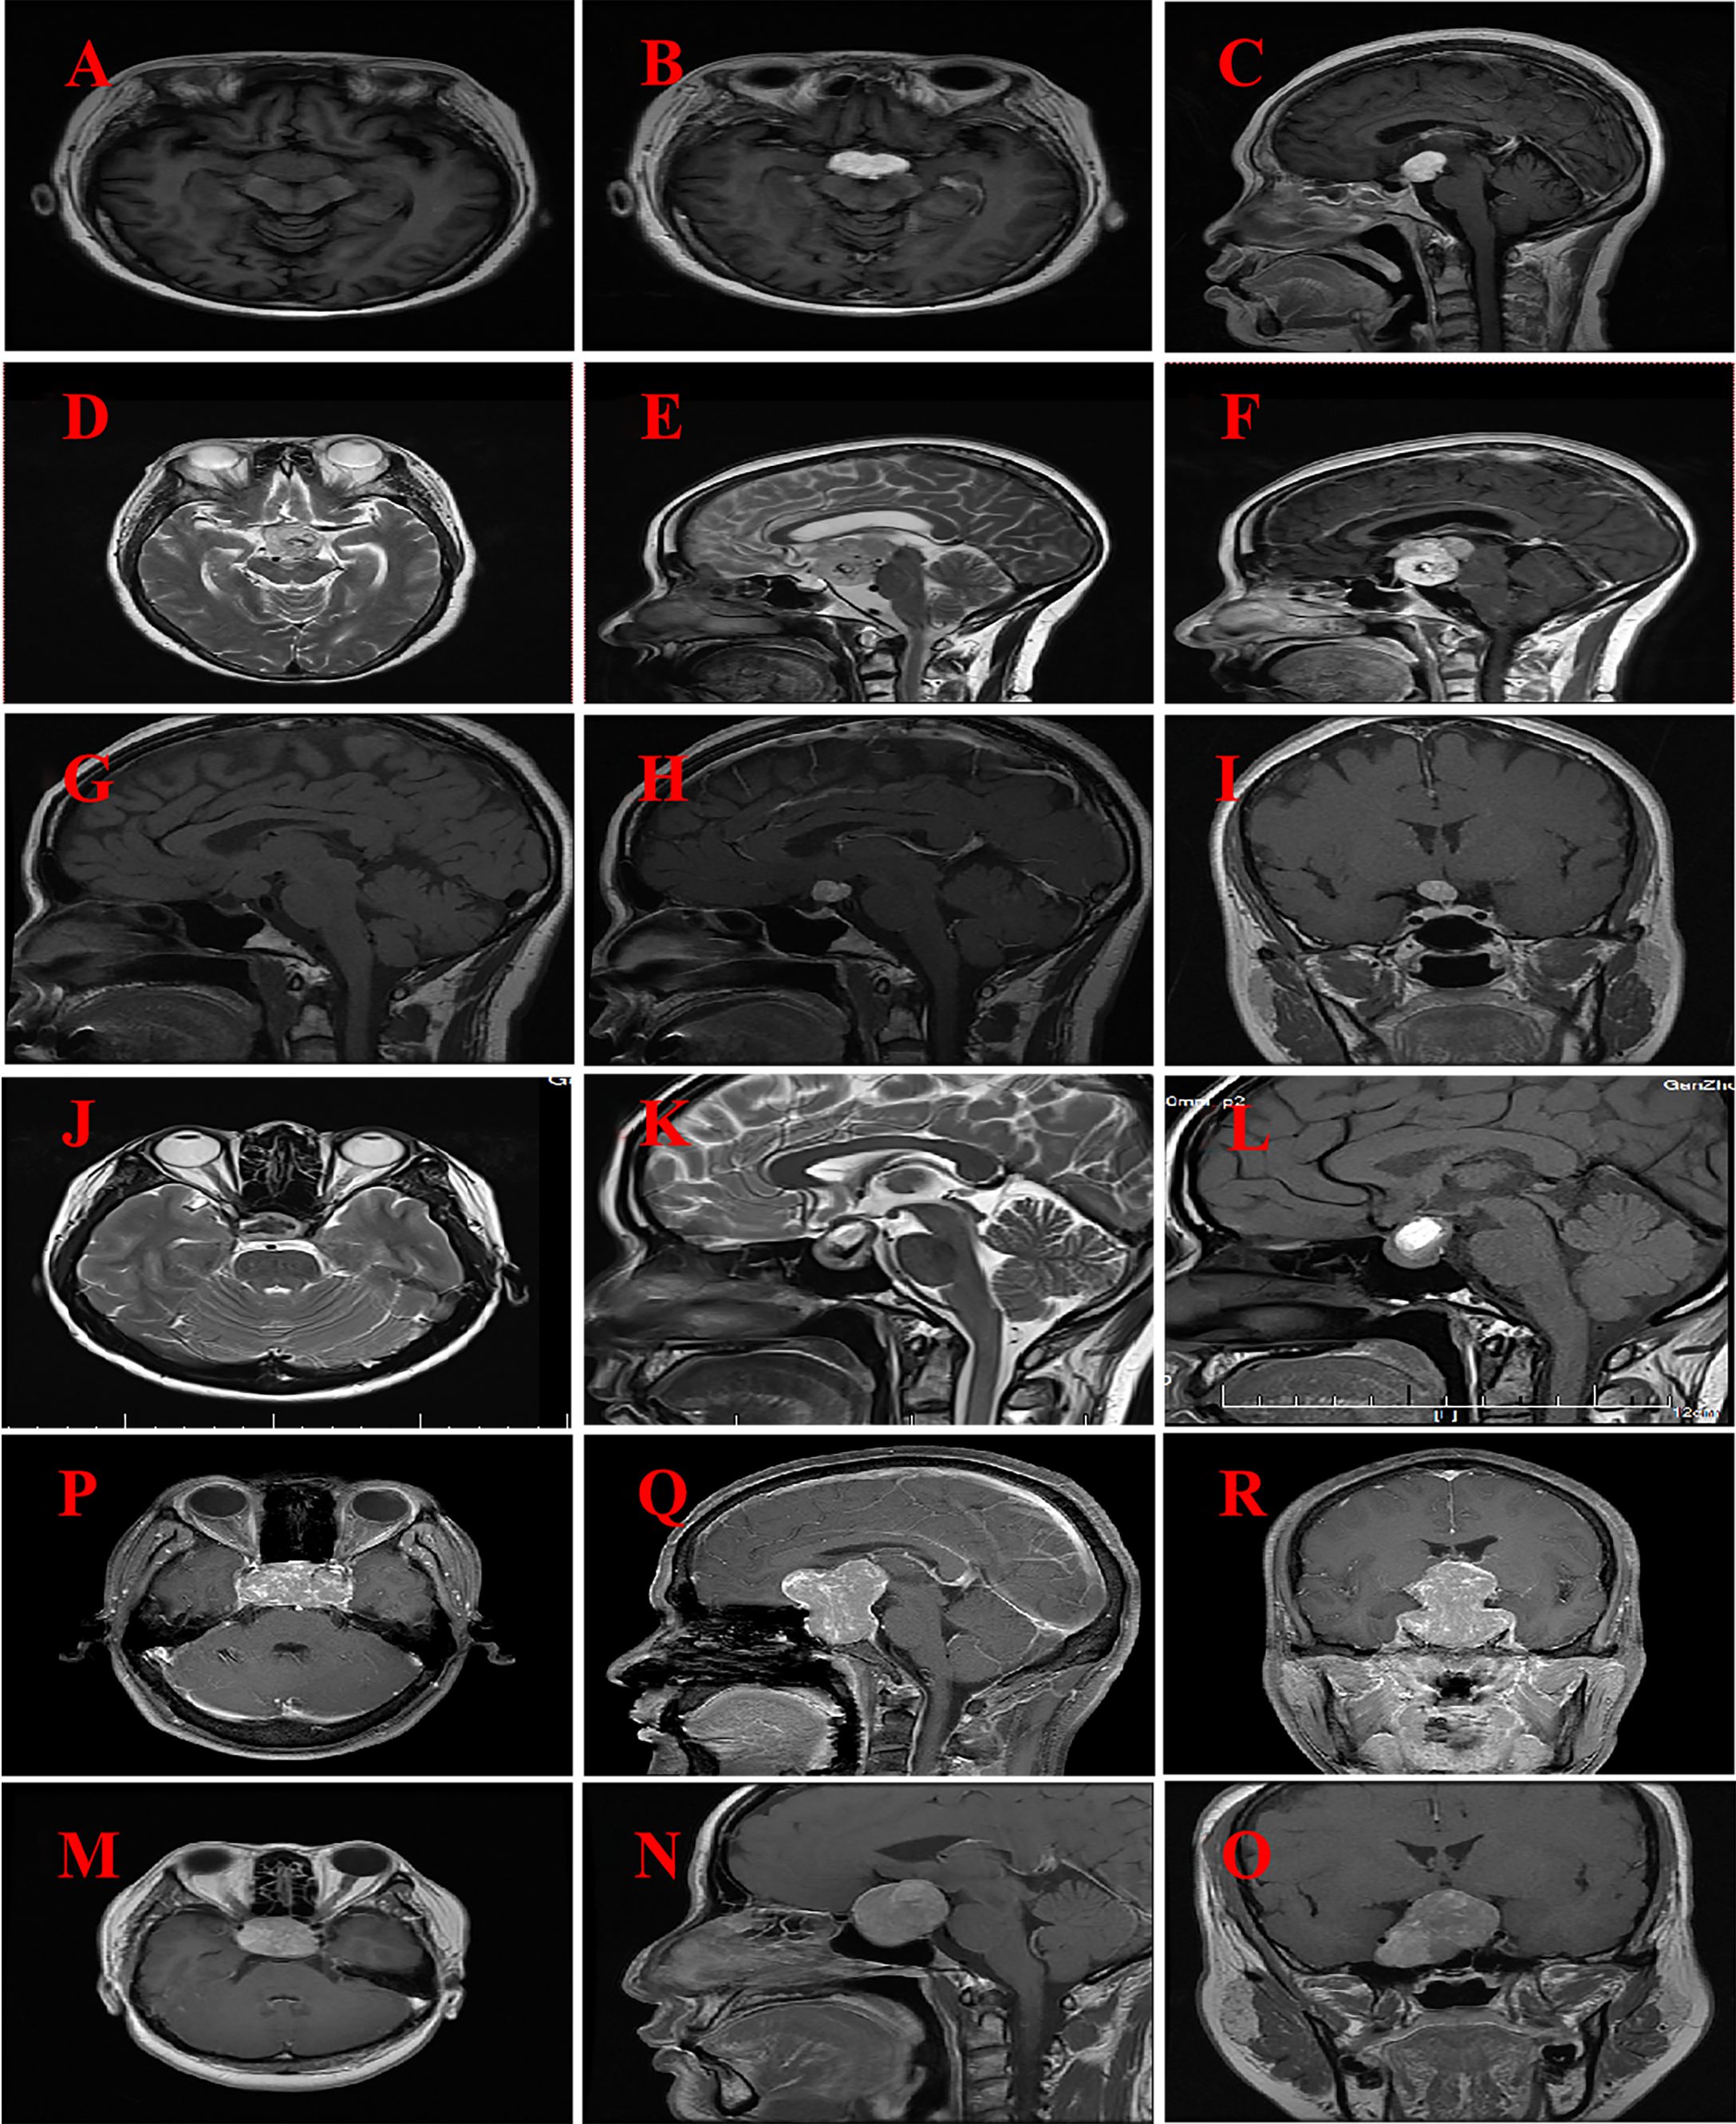

The findings of brain MRI from six patients are presented in Table 3 and Figure 1 . The MRI scan revealed that the tumor predominantly exhibited a spherical morphology with well-defined margins. Among the patients, two presented with suprasellar tumors (Figures 1A–F), while the remaining four patients had tumors situated in the sellar region, encompassing intrasellar, suprasellar, and parasellar components, including two instances of cavernous sinus invasion (Figures 2A–F). In all six patients, the tumors demonstrated iso-intensity on T1-weighted MRI (T1WI). In contrast, T2-weighted imaging (T2WI) showed more varied signal intensities: two cases exhibited slightly decreased signal intensity, two cases showed slightly increased signal intensity, one case presented with equivalent signal intensity, and one case displayed a mixed pattern of high and low signal intensities. On contrast-enhanced MRI, the tumors exhibited either homogeneous or heterogeneous enhancement, with two tumors demonstrating homogeneous enhancement. The dimensions of the tumors were 3.1 cm × 4.5 cm × 5.7 cm and 3.5 cm × 2.7 cm × 4.3 cm, respectively. One tumor displayed signs of calcification, measuring 2.3 cm × 2.7 cm × 3.3 cm. Preoperative imaging diagnosis indicated pituitary adenoma in three cases, craniopharyngioma in one case, and glioma in one case.

Figure 1

MRI imaging for six patients with GCT of the neurohypophysis. (A–C) The imaging reveals a well-defined, rounded lesion in the suprasellar region, characterized by a slightly prolonged T1 signal. Post-contrast enhancement demonstrates uniform and pronounced enhancement of the lesion, which appears to be in close proximity to the optic chiasm. (Case No. 1). (D–F) There are irregular lesions in the supratentorial region, tri-cerebral ventricles, and anterior pontine pools, characterized by slightly prolonged T2 signals and distinct borders. The enhancement scan reveals uneven and significant enhancement, closely associated with compression of the left thalamus and brainstem. (Case No. 2). (G–I) A rounded lesion located in the suprasellar region exhibited iso-intensity on T1-weighted imaging (T1WI), with well-defined margins. Post-contrast imaging demonstrated significant homogeneous enhancement of the lesion, resulting in compression and elevation of the optic chiasm. (Case No. 3). (J–L) Irregular lesions are observed in the sellar and suprasellar regions, characterized by short T2-weighted signal intensities and well-defined margins. Post-contrast imaging reveals heterogeneous enhancement of the lesions, with evidence of compression and elevation of the optic chiasm. (Case No. 4). (M–O) Solid lesions were observed in the saddle and suprasellar regions, exhibiting mild to moderate enhancement upon contrast-enhanced imaging. These lesions demonstrated bilateral invasion of the cavernous sinuses, encirclement of the internal carotid arteries, and upward extension into the suprasellar cisterns and third ventricles. Additionally, there was compression of the pituitary stalks and optic chiasm. (Case No. 5).(P–R) Solid lesions are observed both within and on the saddle. Upon enhanced imaging, these lesions exhibit moderate to significant enhancement, characterized by heterogeneous enhancement patterns. The lesions extend into the cavernous sinuses bilaterally, resulting in compression of the pituitary stalk and optic chiasm. (Case No. 6).